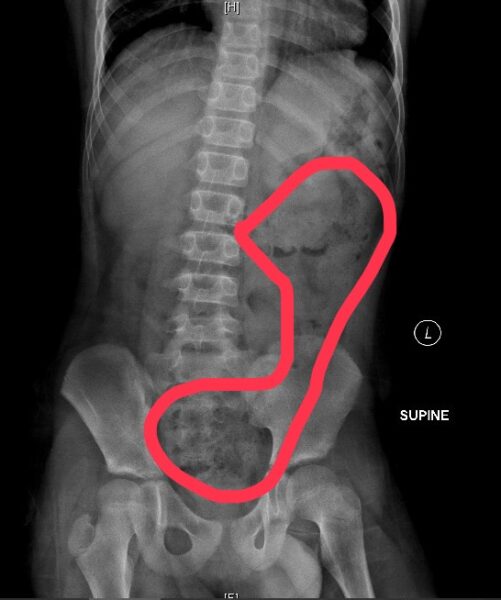

另一名6歲女孩除了肚子痛得直哭叫,腹部並明顯異常脹大,經腹部X光檢查發現她"一肚子大便"!媽媽說她可能剛上小學,還沒習慣上課節奏,有便意也忍著不去廁所,就連幾天沒上大號也記不清,直到症狀嚴重掛急診。